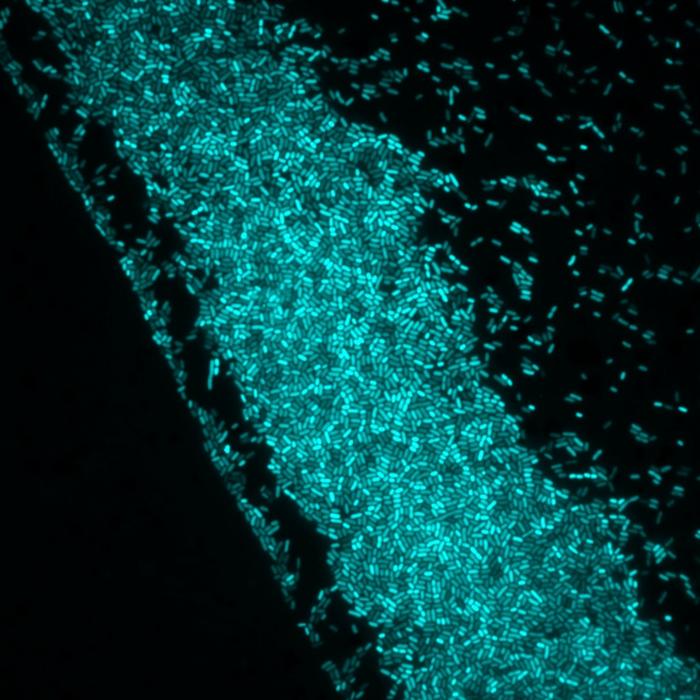

Photo-controlled bacteria - Project EOS

view moreCredit: Politecnico di Milano - Department of Physics

Politecnico di Milano’s research team uses special photo-transducing molecules that irreversibly attach to the bacterial surface. When exposed to light, these molecules alter the electrical potential of the bacterial membrane. Department of Physics professor and EOS project scientific coordinator Giuseppe Maria PaternĂ² said: “This interplay between light and electrical signalling allows us to control key biological processes such as movement, biofilm formation, and antibiotic sensitivity. By manipulating the membrane potential on demand, we can influence antibiotic uptake and restore or even enhance the effectiveness of treatments against resistant strains.”

The team’s initial findings, published in The European Physical Journal Plus (Springer Nature), demonstrate that optomodulation, which is the light-induced modulation of electrical signals, directly affects the absorption of antibiotics. “Using a photosensitive molecule called Ziapin2, the researchers altered the membrane potential of Bacillus subtilis, modulating the action of antibiotics such as Kanamycin (which acts within the cell) and Ampicillin (which targets the cell wall). Under blue light (470 nm), the effectiveness of Kanamycin was significantly reduced, suggesting that membrane potential plays a crucial role in the drug’s uptake. Ampicillin, on the other hand, retained much of its efficacy under illumination” PaternĂ² said.